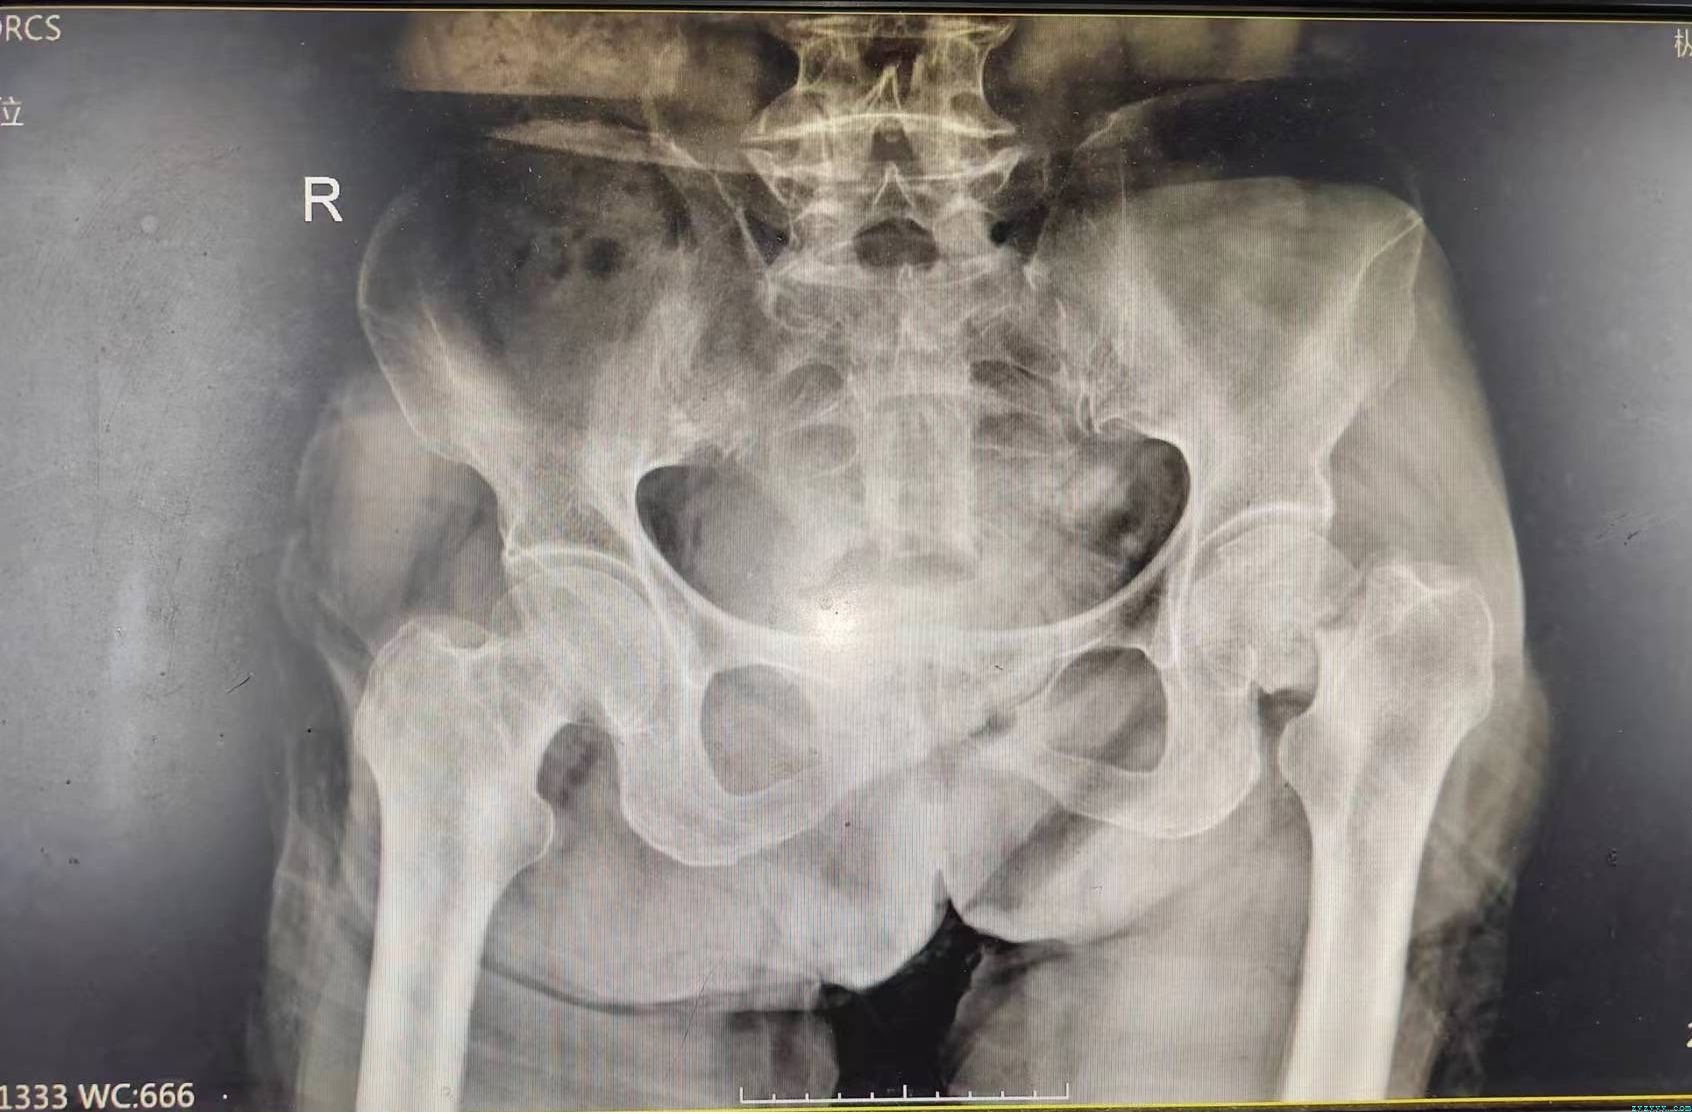

患者朱XX,女,78岁,系“跌伤致左髋部肿痛、活动受限1小时”于6月7日收入院。患者1天前不慎跌伤致左髋部,即感左髋部疼痛,活动受限,进行性肿胀,未予特殊处理,急来我院就诊,门诊检查拟诊断“左股骨颈骨折”收住我科。病程中无昏迷,无恶心、呕吐,无大小便失禁。既往史:患者既往有“慢性肾衰竭 尿毒症期 血液透析状态(2次/周)、高血压病、糖尿病、慢性心力衰竭、胆囊结石”病史,否认肝炎、结核等传染病史,曾行右侧颈内静脉导管置管术,目前右侧颈内静脉长期导管在位通畅,曾行胆囊切除术,否认食物及药物过敏史。入院查体:T 36.8 ℃ P 83次/分 R18次/分 BP205/107 mmHg,神志欠清楚,营养欠佳,痛苦面容,口唇无紫绀,颈软无抵抗,心肺腹(-)。脊柱四肢见专科检查。专科情况:脊柱生理弧度正常,无明显侧弯畸形,左髋部肿胀、畸形,局压痛(+),纵向叩击痛(+),左髋关节活动受限,左下肢较对侧短缩约1.5cm,患肢末梢血运可,皮肤感觉正常。辅助检查:(2023/06/0713:53)骨盆正位左股骨正位:左侧股骨颈骨折。西医诊断:1.(左)股骨颈骨折2.慢性肾衰竭 尿毒症期 血液透析状态3.糖尿病4.高血压病3级(极高危) 5.慢性心力衰竭